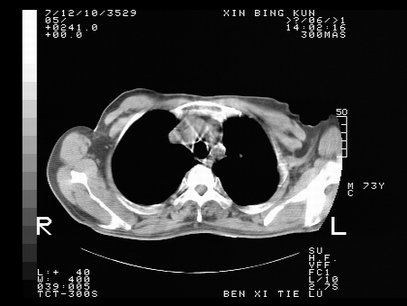

标题: CT10820:男,73岁,病史肺TB,现病史肺炎,直肠CA术后 [打印本页]

双肺间质改变,依据病史双肺多发结节灶考虑转移,少量胸水.

1.两肺结核.2.两肺多发转移瘤.3右侧少量胸腔积液4.主动脉钙化.

双肺多发结节及条片状致密影,右侧少量胸腔积液。临床:直肠ca术后,肺tb病史。综合考虑:1 双肺转移!2 继发性肺结核合并感染!

此人病史较复杂,原有肺结核,直肠癌术后。肺部病灶形态亦呈多形性。因此,不可仅以一种病来解释肺部的病变。双肺多发的类圆形结节灶,结合病史还是首先考虑转移瘤,而双肺其余病灶还需结合化验室检查,结核或肺部感染在无其它检查资料的情况下不好排除。还是那句话----放射科医生不是开照像馆的,我们也是医生,看片一定要多结合临床及其它检查资料。要当一名合格的放射科医生,并不比当一名临床医生容易,我们可别把自已不当医生看。

两肺多发结节影,并见滋养动脉与其相连,考虑 两肺转移. 右侧胸腔积液考虑胸膜转移.

左肺上叶下叶背段,右肺中下叶见多发斑片状、条索状高密度影,兵变周围小结节影形成“树芽”样改变。 左肺上叶舌段近前胸壁处及右肺中叶内侧段见结节影。右侧胸膜腔内见液体密度区。纵隔内未见明确增大淋巴结。考虑左肺上叶舌段近前胸壁处及右肺中叶转移瘤可能性大。两肺继发型肺结核。右侧胸腔积液。